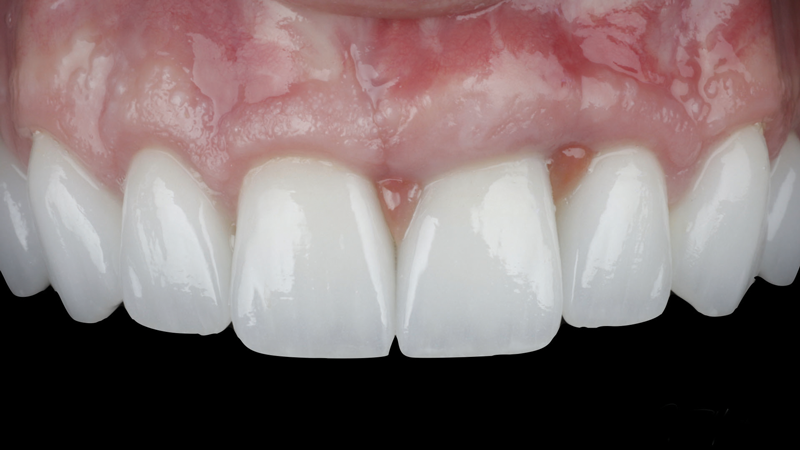

(9.) Postoperative photographs acquired after 2 weeks and 3 months of healing, respectively, demonstrating the reconstitution of an ideal tooth No. 9 marginal position in relation to its contralateral counterpart with increased soft-tissue thickness.

Figure 9

(10.) Postoperative photographs acquired after 2 weeks and 3 months of healing, respectively, demonstrating the reconstitution of an ideal tooth No. 9 marginal position in relation to its contralateral counterpart with increased soft-tissue thickness.

Figure 10